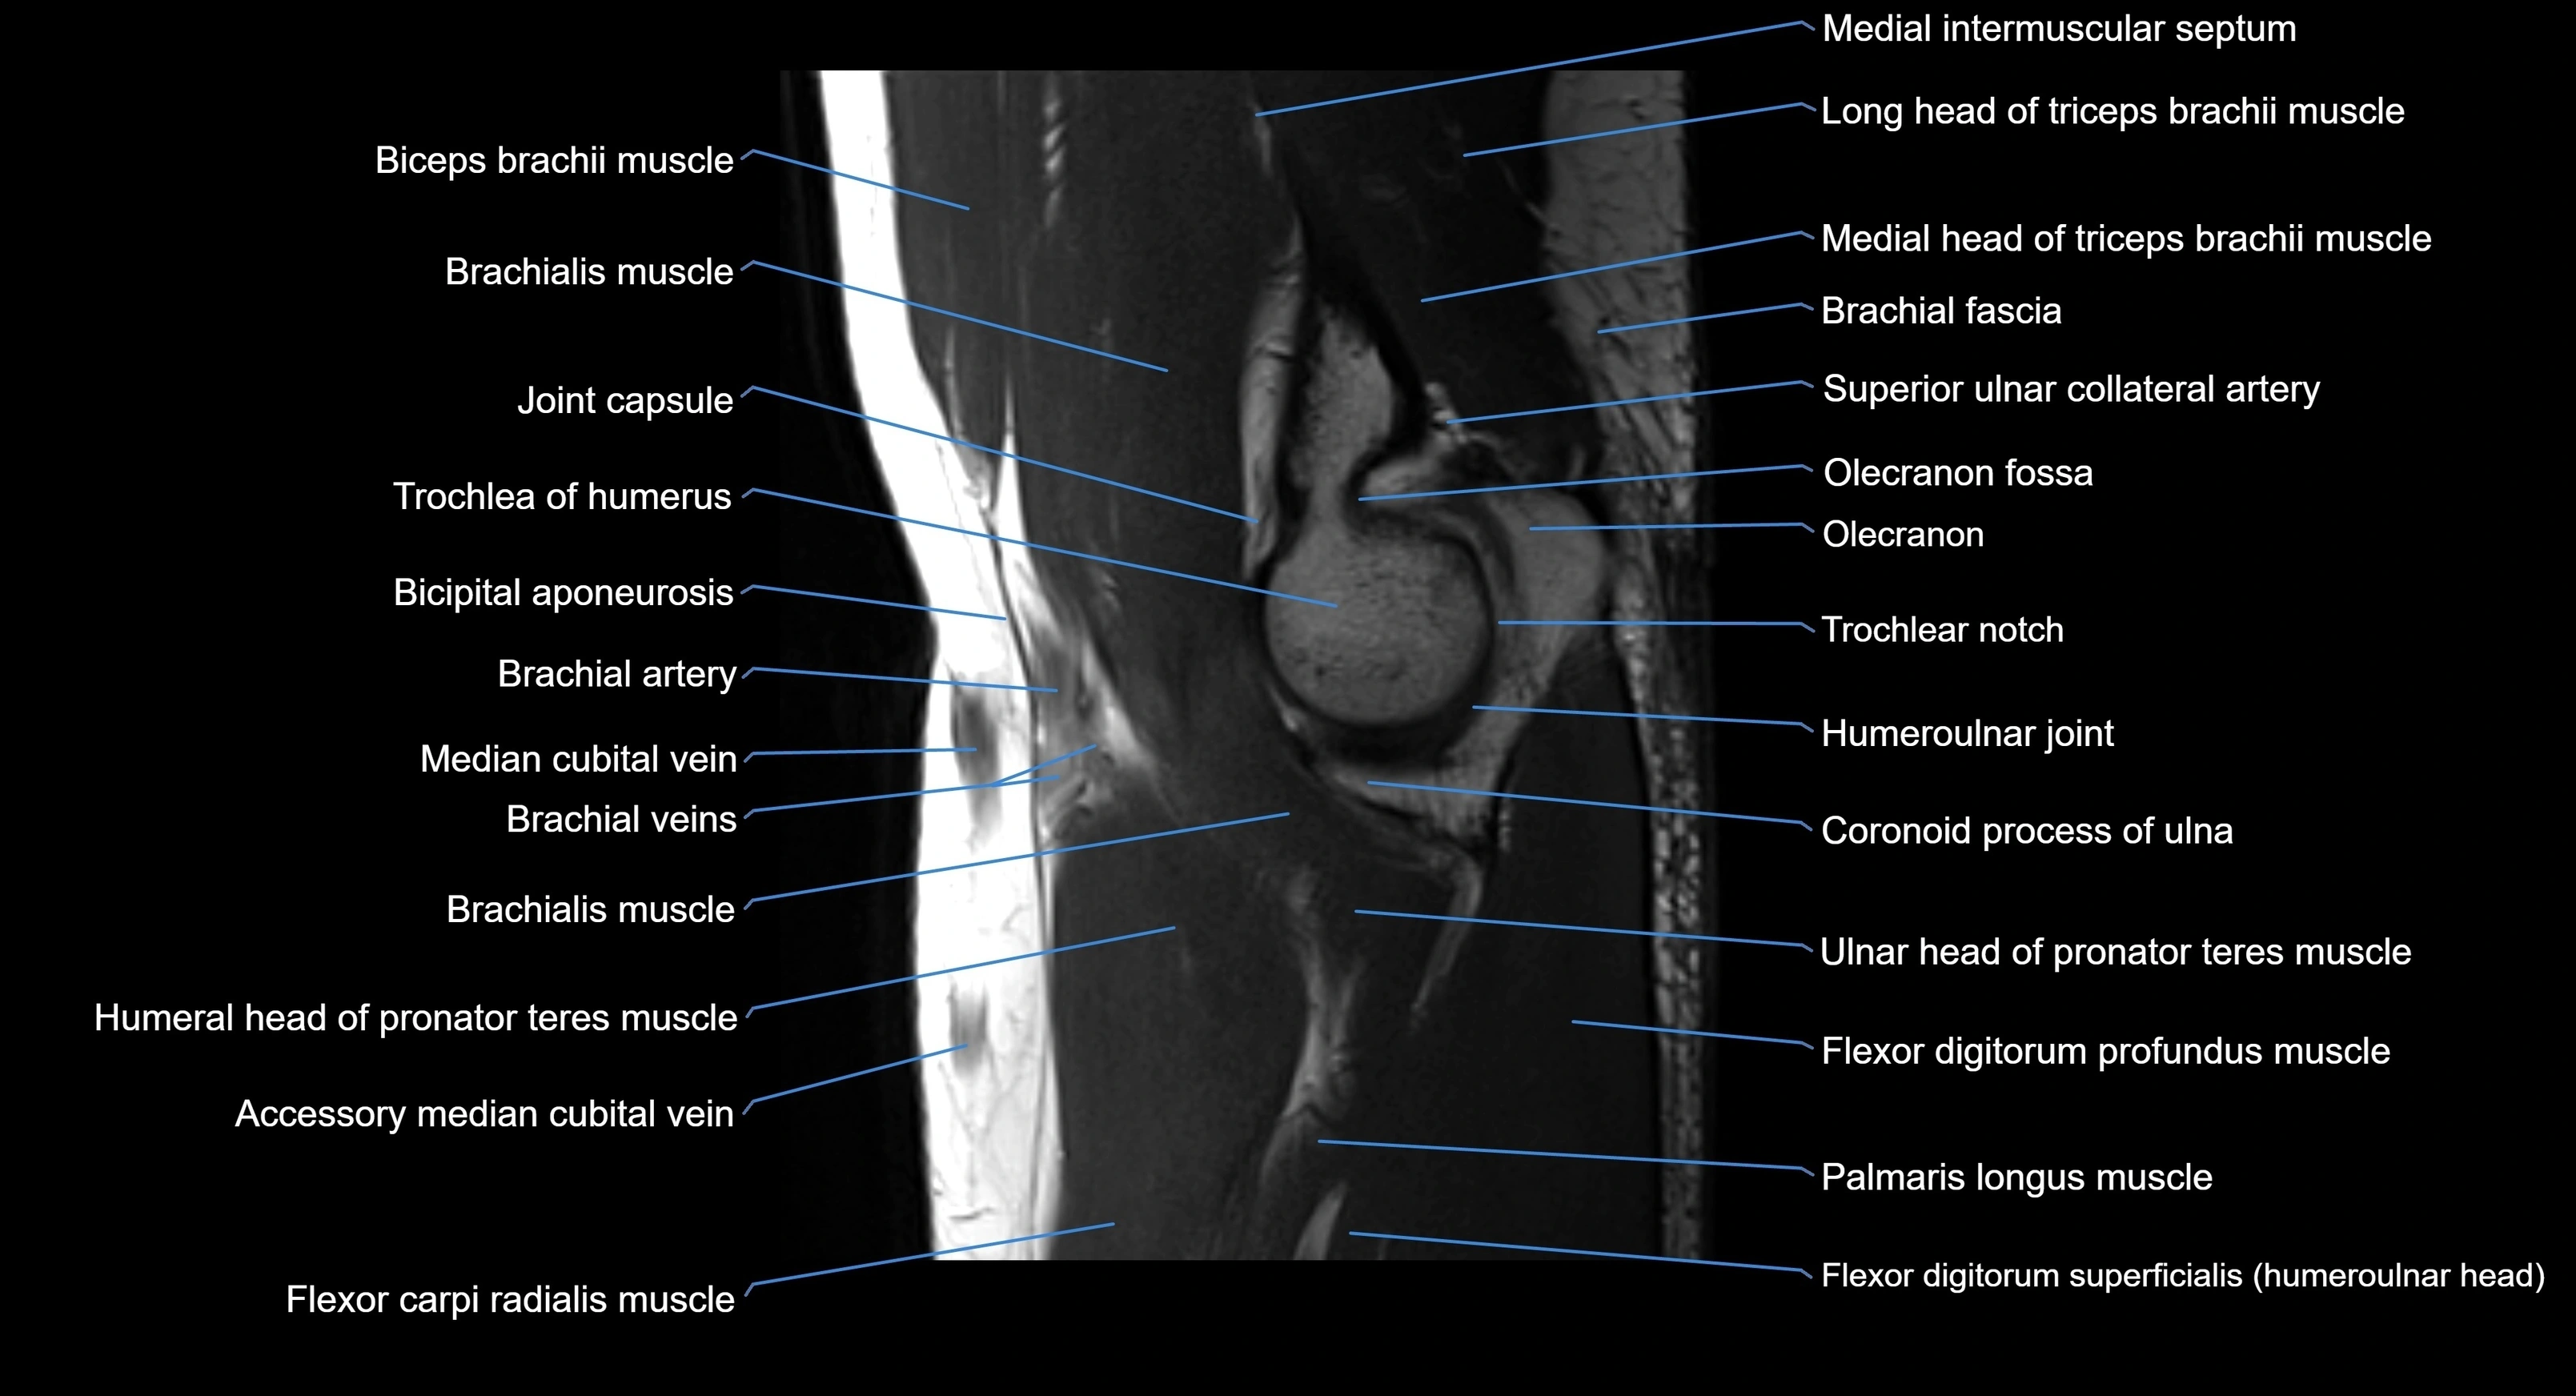

MRI image

image